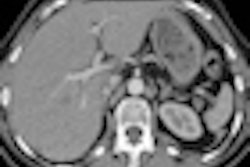

Short axis reconstruction of low dose (at 20% mAs) coronary CT angiography image reconstructed with standard FBP. In bottom image, low-dose CCTA image reconstructed with SAFIRE, demonstrates greatly improved image quality. Images courtesy of Dr. Richard Takx.